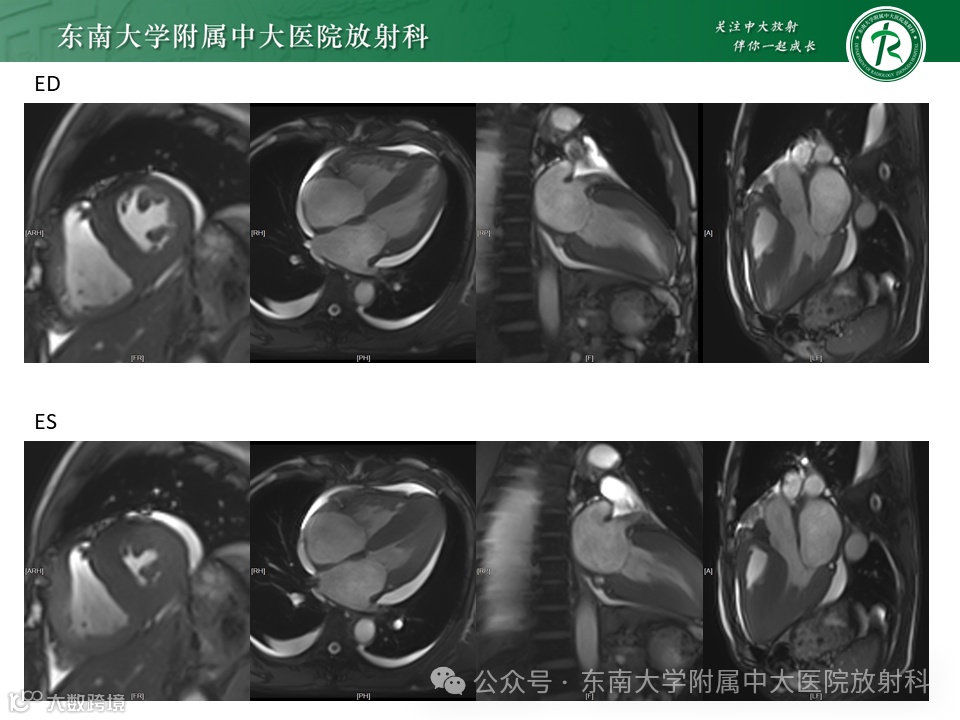

病例1——急性心力衰竭 -

病例2——应激性心肌病 -

病例3——淀粉样变心肌损害